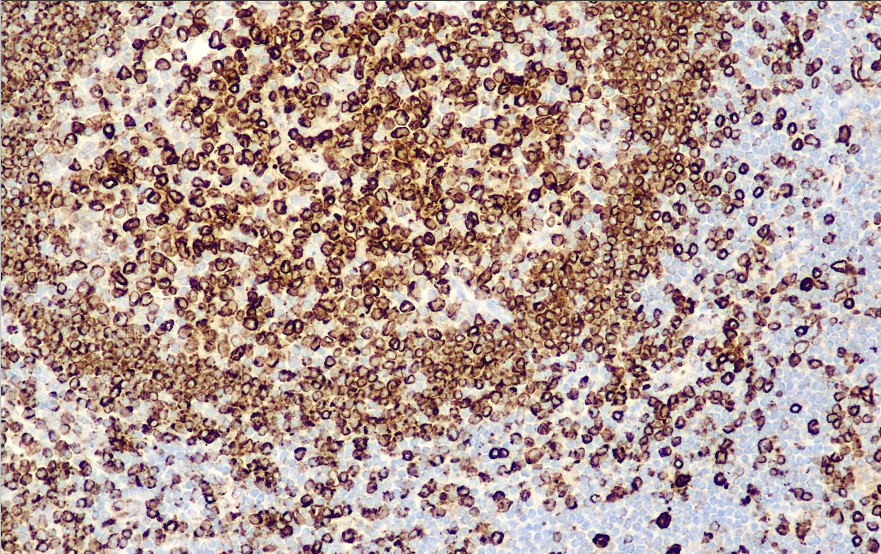

Positive control: tonsils

CD74 is expressed on all B-cells and certain T-cell subclasses (MHC II positive), mainly lymphocytes in germinal centers, with several isoforms (33-41 KDa), and is a constant chain of HLA-DR. This antibody is mainly used to label B cells and tumors of their origin, T cell lymphomas are rarely expressed, the staining pattern is cytosolic, but paranuclear granular staining is seen, which helps in the study of lymphomas and leukemias.

CD74 Antibody Reagent binds specifically to CD74 molecular antigen. Immunohistochemistry kits containing CD74 Antibody Reagent are suitable for the precise diagnosis of lymphoma, leukemia, atypical fibro-yellow sarcoma and malignant fibrous histiocytoma.